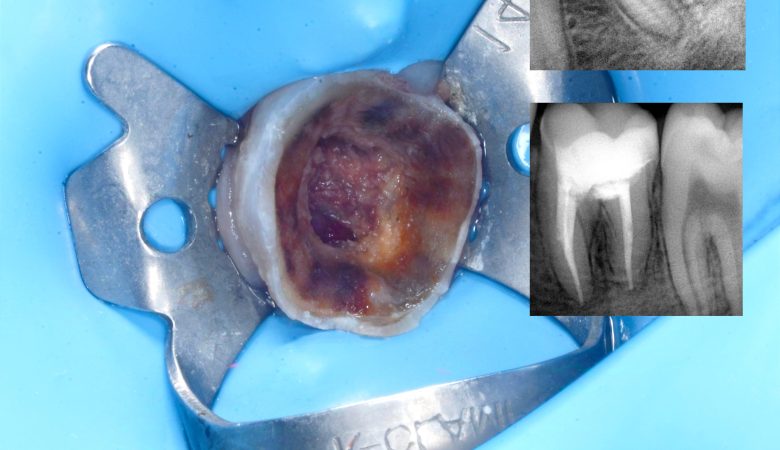

Initial Condition:Preoperative condition of the tooth showing extensive decay and compromised structure. Preparation and Caries Removal:Careful preparation and removal of decay reveals deep caries extending into the pulp chamber. Vital Pulp Therapy & Immediate Dentin Sealing (IDS):Vital pulp therapy performed…